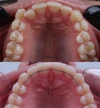

Diş Çapraşıklığı

Zirkonyum uygulamalar

Porselen uygulamaları

Laminate veneer